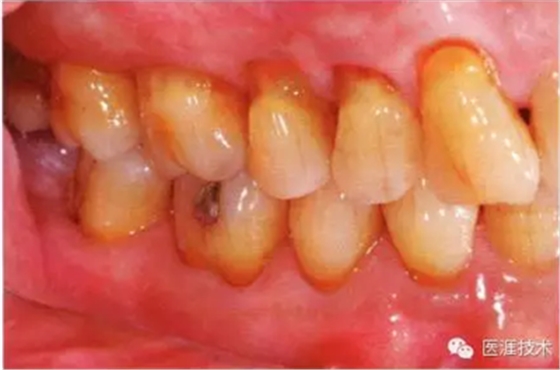

55歲牙周炎男性的臨床照片

55歲男性抽煙患者(1天20支、抽煙35年)。菌斑控制得不好。通過牙周探診,全頜有4~9mm的牙周袋,有1~3度的根分叉部病變。通過X光片觀察,上頜前牙中度牙槽骨吸收,其他地方有中度牙槽骨吸收。受吸煙影響,牙齦纖維性肥厚,呈紅黑色。牙齦幾乎沒有浮腫和發(fā)紅,所以這個病例是從外觀上無法預(yù)測病癥嚴重程度的病例。